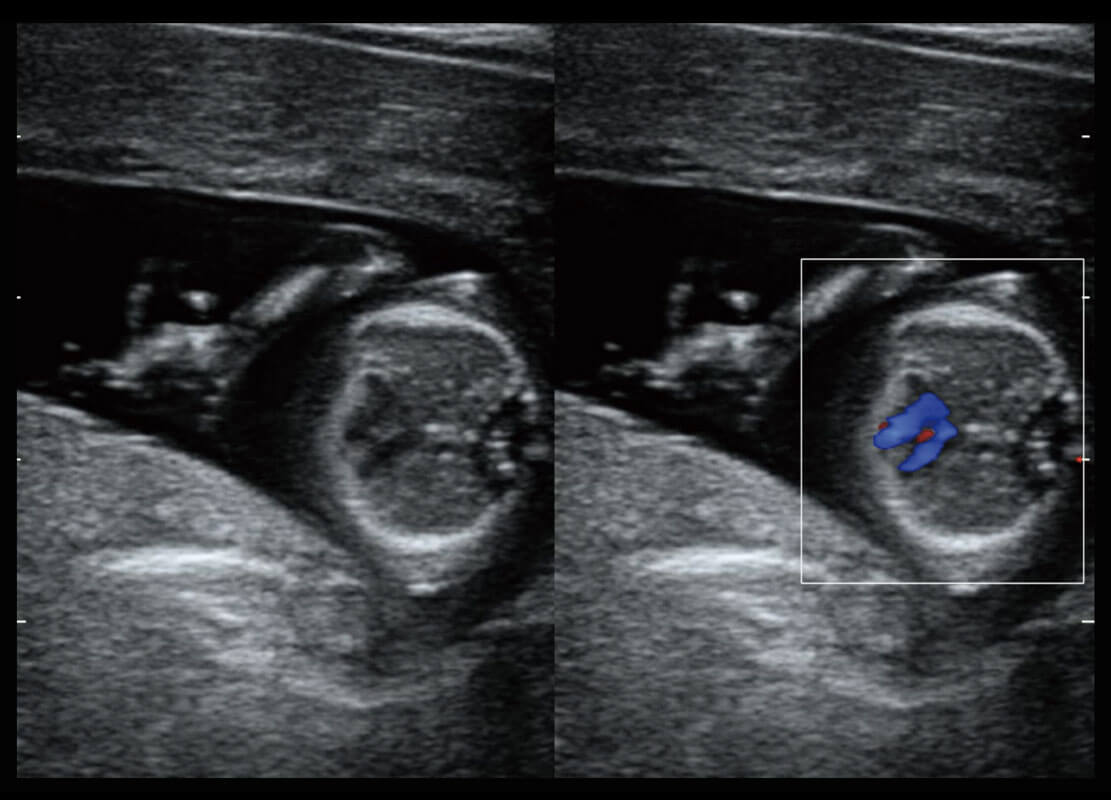

盆底超声

P60为盆底超声检查提供应用方案,多种腔内及腹部容积探头提供从二维、三维到四维的优异图像品质,实时快速三维容积数据获取,专业的测量工具包等人性化设计,为超声医生诊断提供有力保障。

S-Pelvic

能够简化盆底检查的操作流程,可在二维模式及三维成像模式下实现一键自动提取出标准切面、自动识别当前切面、自动测量,提升盆底检查的高效性,同时也能让青年医生快捷的获得准确的检查结果。